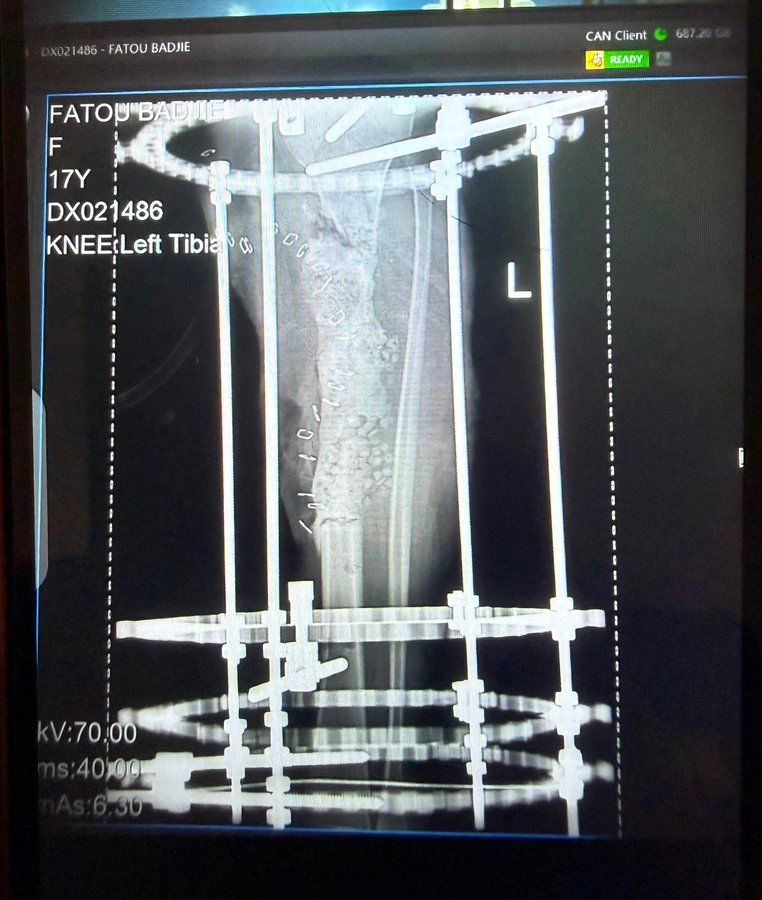

The most clinically significant and technically demanding case of the mission involved a 17-year-old female presenting with a severely comminuted open tibial fracture of the left leg. The wound had remained open for seven weeks prior to the mission. Preoperative imaging – doppler - confirmed a single-vessel limb — a profoundly hostile reconstructive environment — with extensive soft tissue loss overlying the fracture site and 15 cm segmental bone loss. Free flap reconstruction was the only viable option to salvage the limb and avoid amputation.

The Operation

Operating under the Zeiss surgical microscope available at EFSTH that was found not used in the hospital and was checked preoperatively and made sure it is functioning — a single-operator instrument without assistant binocular access — a free flap reconstruction was performed. Personal microsurgical instruments brought from the UK were used, including microsutures carried by the operating surgeon. A vein graft was incorporated to bridge the vascular defect created by the single-vessel anatomy. An old bipolar coagulation machine was donated to the hospital to support future cases.

Postoperative Course and Flap Compromise

The immediate postoperative period highlighted the critical infrastructure gaps that currently preclude routine microsurgery in The Gambia. Structured flap monitoring protocols do not exist at EFSTH, and dedicated postoperative nursing observation for vascular compromise is unavailable. On postoperative days one and two, the patient was transported — against explicit medical instruction — to a separate hospital facility for plain radiographs, exposing the limb to uncontrolled positioning and pressure. On day three, the patient was found lying directly on the vein graft on the open ward, causing positional compression of the anastomosis. This led to compromise of the flap.

- Ilizarov Fixation Expertise: The orthopaedic team has established Ilizarov frame skills — an essential component of the orthoplastic approach to complex tibial reconstruction.